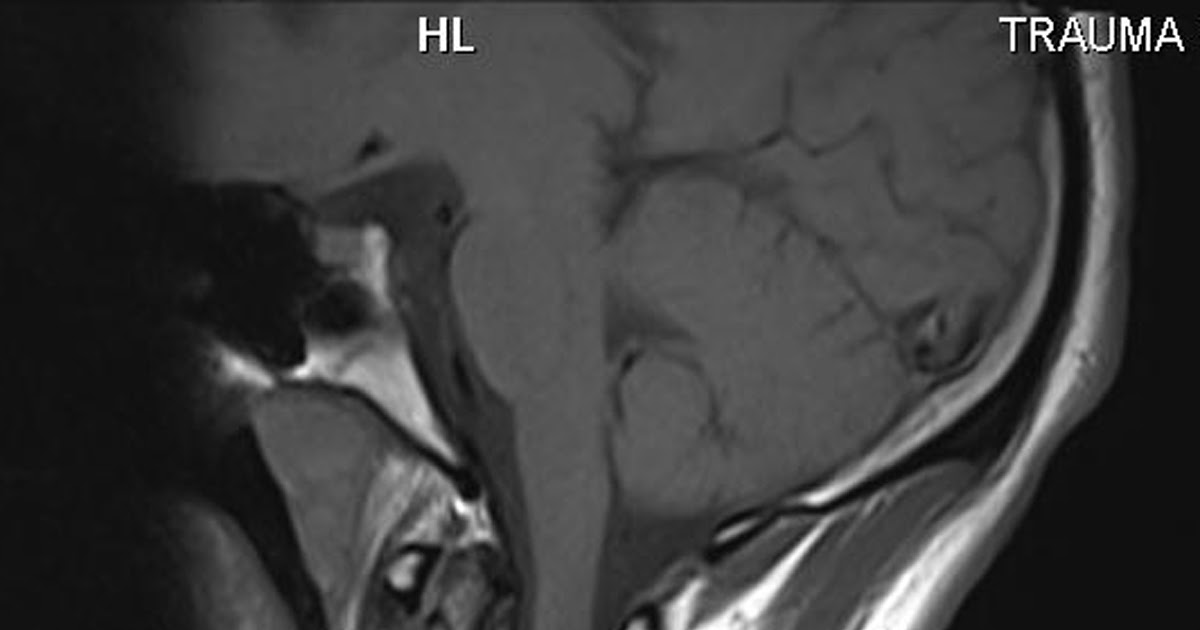

From postgad.blogspot.com

Post Gad Dens Fracture What Is A Dens Fracture It can be fractured, dislocated or compressed by trauma, causing serious complications such as brain stem damage or spinal cord injury. The odontoid process, or dens, is a bone that connects the atlas and axis vertebrae in the neck. Odontoid fractures are relatively common fractures of the c2 (axis) dens that can be seen in low energy falls in elderly. What Is A Dens Fracture.